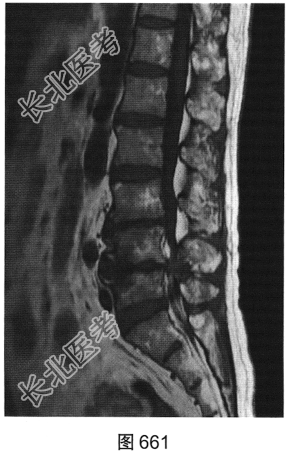

- 多项选择题3.[提示]患者行腰椎MRI检查,如图660~图663所示。患者MRI的T2压脂像上, 部分椎体上、下缘高信号提示( )

A、椎体感染所致的骨髓水肿

B、肿瘤侵蚀破坏

C、椎体轻度压缩骨折

D、脊椎结核

E、退变所致的终板炎

F、椎体脂肪化

- 多项选择题4.综合X线、CT和MRI图像,该患者有以下哪些腰椎退变征象( )

A、终板炎

B、腰椎间盘突出

C、许莫结节

D、黄韧带肥厚

E、腰椎管狭窄

F、腰椎间盘脱出,髓核游离